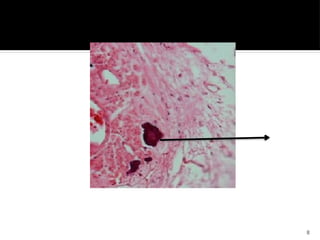

Histopathology

 An internal resorption lesion mainly

consists of granulation tissue.

 The pulpal connective tissue is highly

vascularized with varying degrees of

inflammation, infiltrated by lymphocytes,

macrophages, neutrophilic leukocytes, and

plasma cells.

 Neutrophils and macrophages are

attached to the mineralized dentin surface.

 “Resorptive bays” with numerous

odontoclasts are also seen